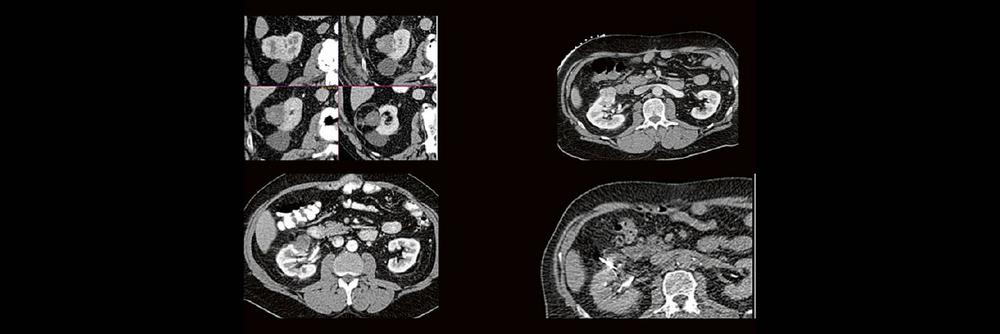

Die Anwendung von ablativen Verfahren hat sich in der klinischen Praxis etabliert. Nierentumoren bieten sich für den Einsatz von RFA und Mikrowelle an. Im Dietrich Bonhoeffer Klinikum Neubrandenburg blicken wir auf 15 Jahre Erfahrung mit mehr als 100 RFA/Mikrowellenablationen von Nierentumoren zurück. Im Vortrag werden die eigenen Erfahrungen und Ergebnisse vorgestellt.

Dabei wird auf die Indikationsstellung, Vorbereitung, Durchführung, Nachuntersuchungsintervall, Komplikationen und Erfolgsrate eingegangen.

Back to the roots! Gute Kenntnisse der Anatomie sind der Schlüssel zur guten Planung, Durchführung und richtigen Diagnosestellung im CT des Abdomens. Lernen sie unverkrampft

• schnelle Orientierungspunkte für den Alltagsgebrauch

• richtiges Kontrastmittel-Timing im Bild erkennen

• Anatomie in Pathologie übersetzen

Haben Sie es erkannt? Probieren Sie selbst im lockeren Fallquiz zum mitraten.